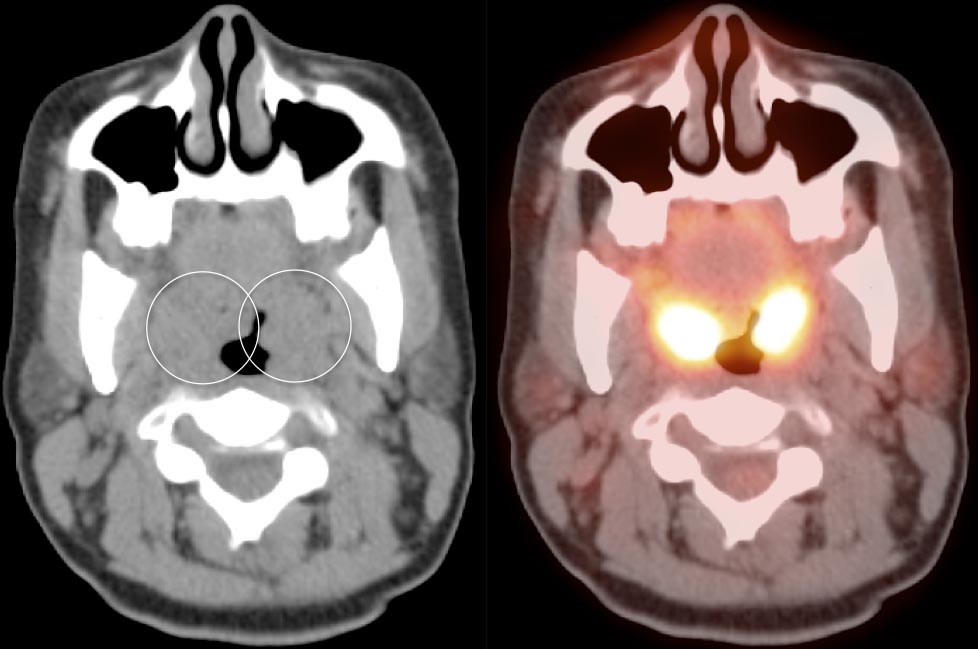

Palatine Tonsils

The palatine tonsils frequently demonstrate very intense metabolic activity.

Interpretation of tonsillar uptake is depends on the clinical presentation of the patient, the degree of FDG uptake, the size of the tonsils and the bilateral or unilateral nature of the findings.

- Bilateral and fairly symmetric FDG-uptake in non-enlarged palatine tonsils is almost always a normal finding.

- Bilateral and fairly symmetric FDG-uptake in enlarged palatine tonsils is nearly always inflammatory in nature (although can occasionally be seen with lymphoma).

- Unilateral or asymmetric increased FDG uptake within one palatine tonsil warrants careful and detailed assessment (addressed in detail, here).